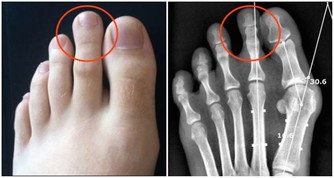

這是腎功能在逐步衰退的信號,有時還會伴隨著腳痛、腰痛、尿頻等症狀,工作過於勞累的人尤其要注意,要做到勞逸結合,避免過度疲勞,少飲酒,少吃生薑、辣椒等刺激性強的食物。